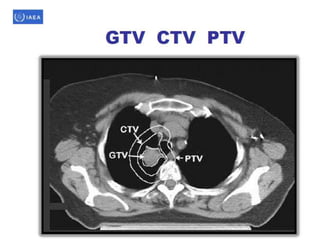

Volume definition

• Prerequisite for 3-D treatment planning.

• ICRU reports50 & 62 define & describe target

& critical structure volumes.

• volumes defined prior to treatment planning

– Gross tumor volume (GTV).

– Clinical target volume (CTV).

• Defined during the treatment planning process

– Planning target volume (PTV).

– Organs at risk.

• As a result of treatment planning, volumes described.

– Treated volume (TV).

– Irradiated volume (IRV).